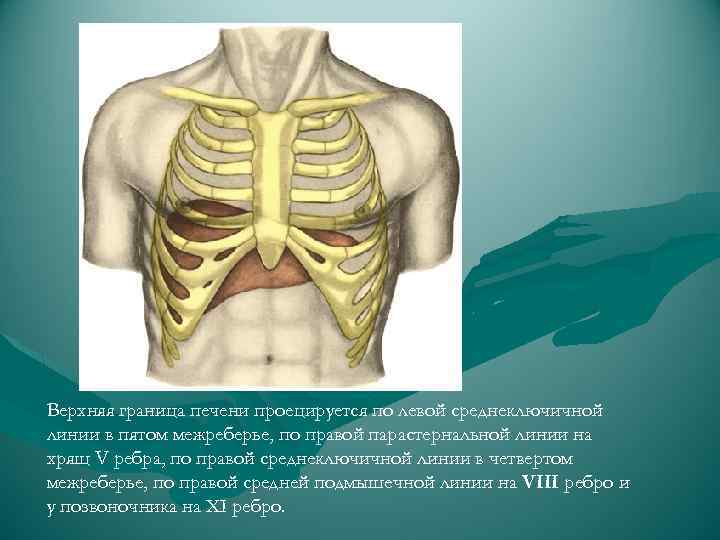

Верхняя граница печени проецируется по левой среднеключичной линии в пятом межреберье, по правой парастернальной линии на хрящ V ребра, по правой среднеключичной линии в четвертом межреберье, по правой средней подмышечной линии на VIII ребро и у позвоночника на XI ребро.

Верхняя граница печени проецируется по левой среднеключичной линии в пятом межреберье, по правой парастернальной линии на хрящ V ребра, по правой среднеключичной линии в четвертом межреберье, по правой средней подмышечной линии на VIII ребро и у позвоночника на XI ребро.